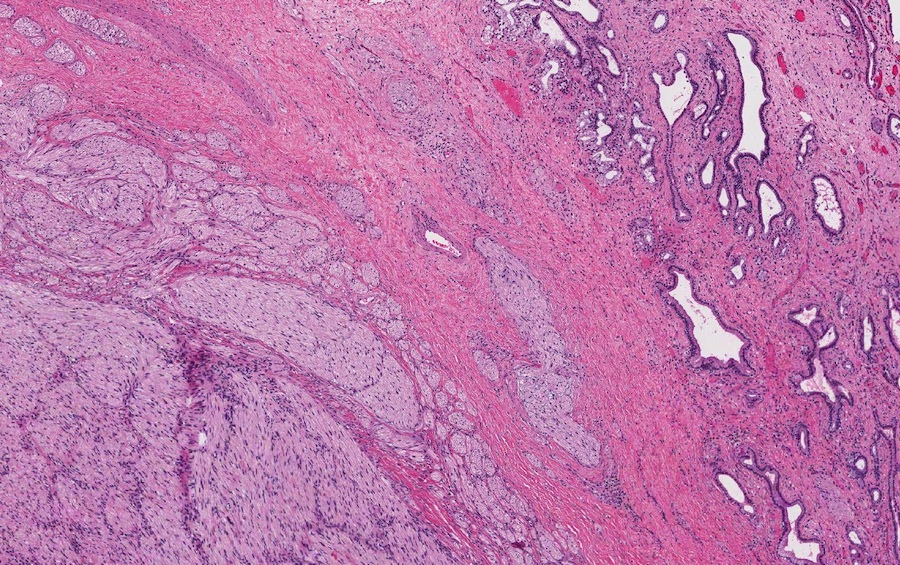

Microscopic images:

Microscopic images:

Both cases showed disorganized and thickened nerve bundles composed of spindle shaped cells, without atypia. Case A also showed a focal foreign body type giant cell reaction adjacent to the disorganized nerve bundles and a strongly immunoreactive S100 stain.

Histology typically shows hyperplastic nerve bundles, positive for S100.

Microscopic images:

Microscopic images:

Both cases showed disorganized and thickened nerve bundles composed of spindle shaped cells, without atypia. Case A also showed a focal foreign body type giant cell reaction adjacent to the disorganized nerve bundles and a strongly immunoreactive S100 stain.

Histology typically shows hyperplastic nerve bundles, positive for S100.